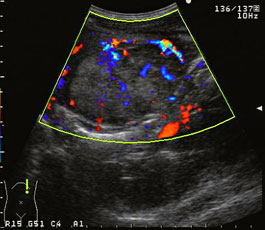

・肝細胞癌の結節型腫瘍:バスケットパターン

肝細胞癌などの多血性肝腫瘍で特徴的に認められる血流パターンの一つ。超音波のカラードプラ検査で、腫瘍の辺縁部から内部に向かって拍動性の血流信号が網目状に見えるもので、このパターンは腫瘍周囲の線維性被膜に存在する血管(動脈や門脈)が腫瘍を包み込むように走行しているために出現します。進行肝細胞癌の膨張性発育で周囲肝組織が圧迫され、線維化と血管増生が進行した状態を反映したものです